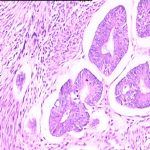

子宫腺肌症相关检查

子宫腺肌症常用的检查有:妇科检查、CA-125、CEA、AFP、激素六项、B超、3D腹腔镜(诊断治疗兼为一体),病理检查(术后)。根据腺肌症症状及临床表现、体征及相关检查可确诊。